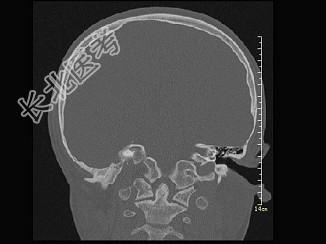

- 单项选择题女,12岁, 自幼右侧听力丧失,CT检查如图, 下列说法错误的是 ( )

A、右侧外耳道闭锁

B、右侧外耳道不发育

C、右侧慢性化脓性中耳炎

D、右侧乳突为板障型

E、应诊断为先天性外耳道畸形